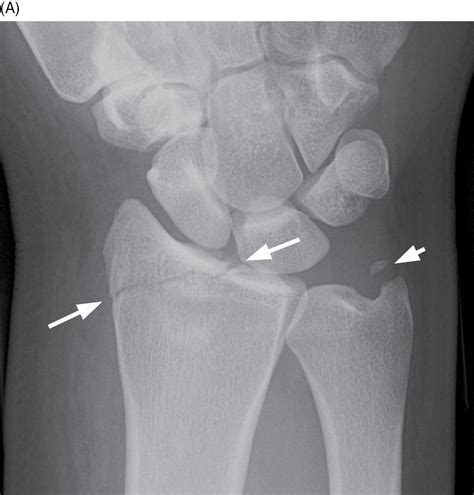

• Imaging Tests: X-rays are the primary diagnostic tool for identifying fractures. In some cases, additional imaging tests like CT scans or MRIs may be required for a more detailed view.

Imaging tests are crucial for determining the type and severity of the fracture, which will guide the treatment plan.

• Distal Ulna Fracture: Occurs near the wrist joint.